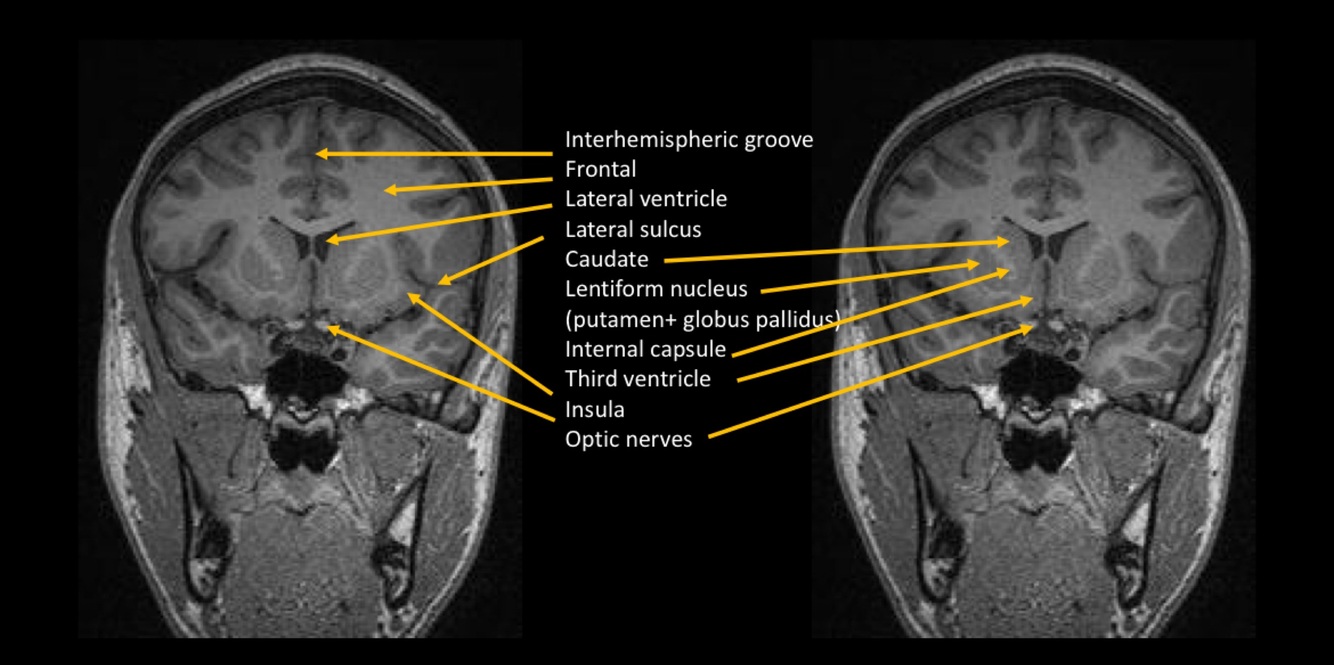

¿Qué técnica observamos?

RESONANCIA MAGNÉTICA